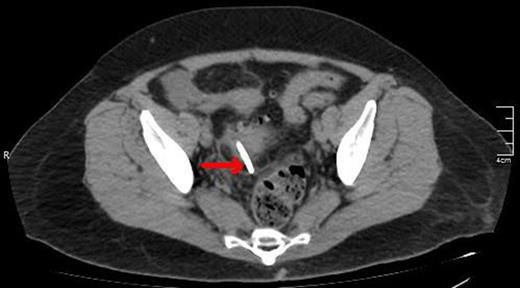

A lower CT view of the same patient showing the stent (red arrow).